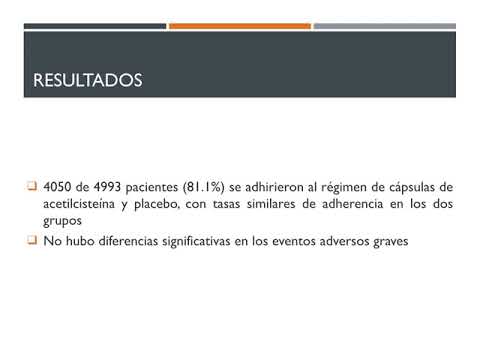

Resultados luego de la angiografía con bicarbonato de sodio y acetilcisteína. Residencia de Cardiología. Hospital C. Argerich. Buenos Aires